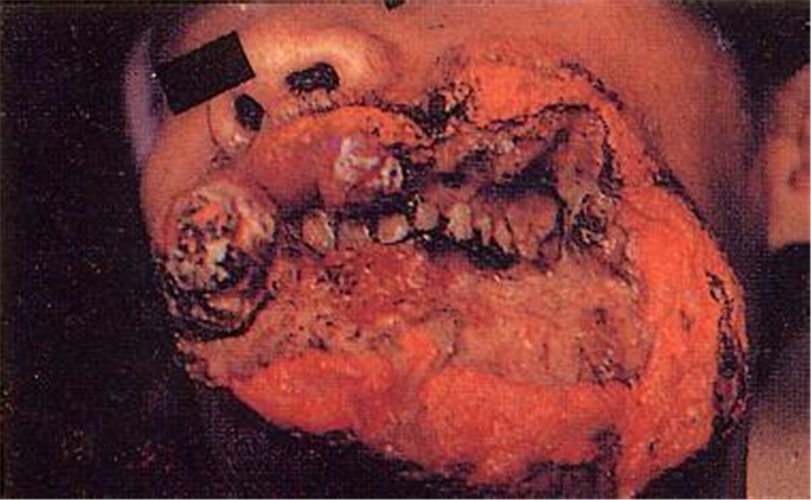

頰癌圖片

十分嚴重的頰癌

女性頰癌潰爛

女人頰癌潰爛